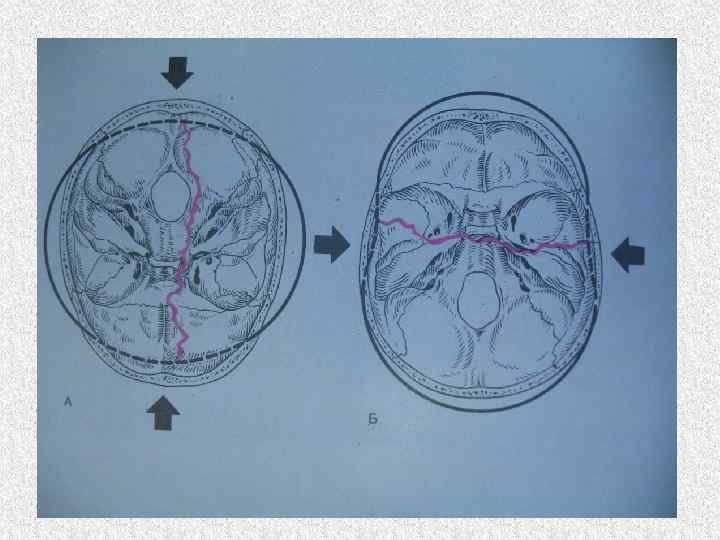

Переезд головы вызывает сокрушительный перелом черепа

Сдавление между двумя автомобилями Сдавление между а/м и тупым предметом • Одна фаза • Повреждения – размятие мягких тканей, переломы костей черепа, ребер, конечностей. Разрывы внутренних органов. • Разрывы одежды, наложения на одежде